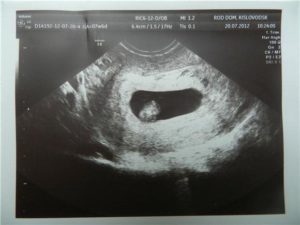

На данном этапе развития плодного яйца можно обнаружить хорион кольцевидный. Что это такое?

На осмотре при помощи ультразвукового датчика можно обнаружить плодное яйцо. Стоит отметить, что эмбриона на этом сроке еще не видно. Верхняя оболочка плодного яйца прикреплена к эндометрию по всей своей площади. Именно в этом случае можно говорит о том, что имеет место кольцевидный хорион.

Подобное состояние верхней плодной оболочки свойственно ранним срокам беременности. Данного рода образование преобразуется примерно на 8 неделе с момента оплодотворения.

Данное образование нельзя определить при вагинальном осмотре. Хорион – это образование, которое можно увидеть только при ультразвуковом обследовании. Всегда в протоколе УЗИ специалист описывает состояние данной структуры, ее расположение и особенности.

Единственным методом диагностики прикрепления и предлежания хориона является УЗИ! Его проводят на ранних сроках, когда уже можно диагностировать отклонения и предупреждать развитие осложнений.